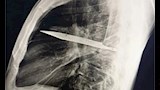

وأظهرت الفحوص السريرية أن الجزء الأيمن من صدره لا يتمدد بالكامل أثناء التنفس، فيما كشفت الأشعة السينية وجود شفرة سكين كبيرة عالقة في تجويف الصدر، ممتدة من الظهر إلى مقدمة القفص الصدري، ومحاطة بطبقات من القيح والأنسجة الميتة.

وتبين أن الرجل تعرض قبل ثماني سنوات لطعنات متكررة في الصدر والظهر والبطن والوجه خلال مشاجرة عنيفة، واكتفى وقتها بتلقي إسعافات أولية للجروح السطحية دون إجراء فحوص تصويرية.